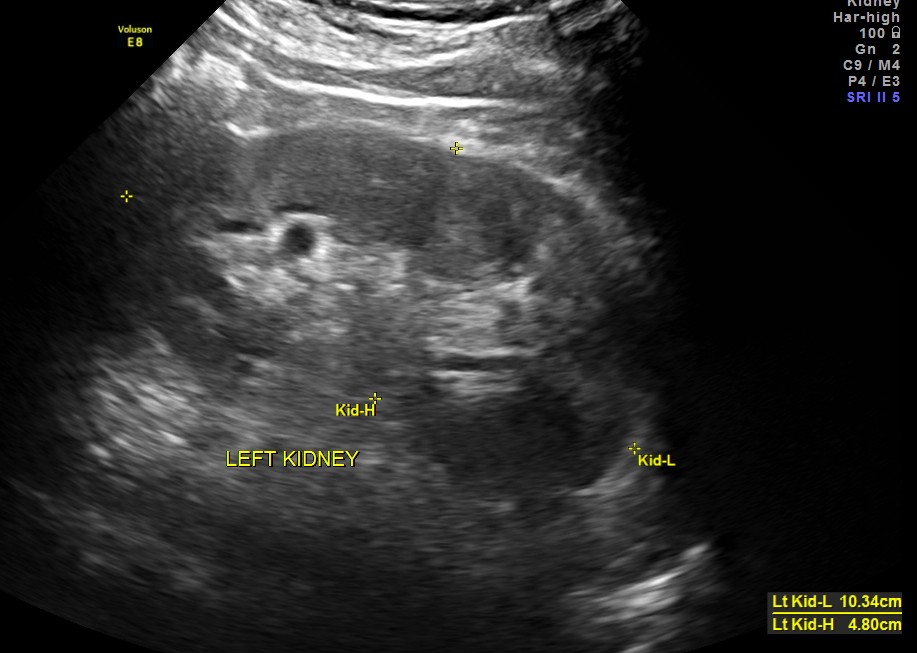

Clinically he had uncontrolled systemic hypertension and mildly elevated s. creatinine of 1.7 mgms/dl.

The diagnosis offered was multiple liver secondaries with incidental finding of shrunk right kidney with probable reduced function.